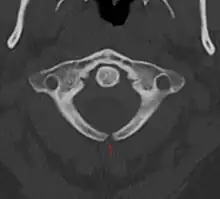

Spină bifidă ocultă

Este forma cea mai ușoară(ascunsă) a spinei bifide.[1] La această afecțiune, cum se vede și în imaginea radiografiei, partea exterioară a vertebrelor nu este complet sudată.[2] Despicătura dintre vertebre este atât de măruntă încât măduva spinării nu herniază. Pielea în zona leziunii poate să apară normală dat poate să crească și câteva fire de păr sau să apară un nev.[3]